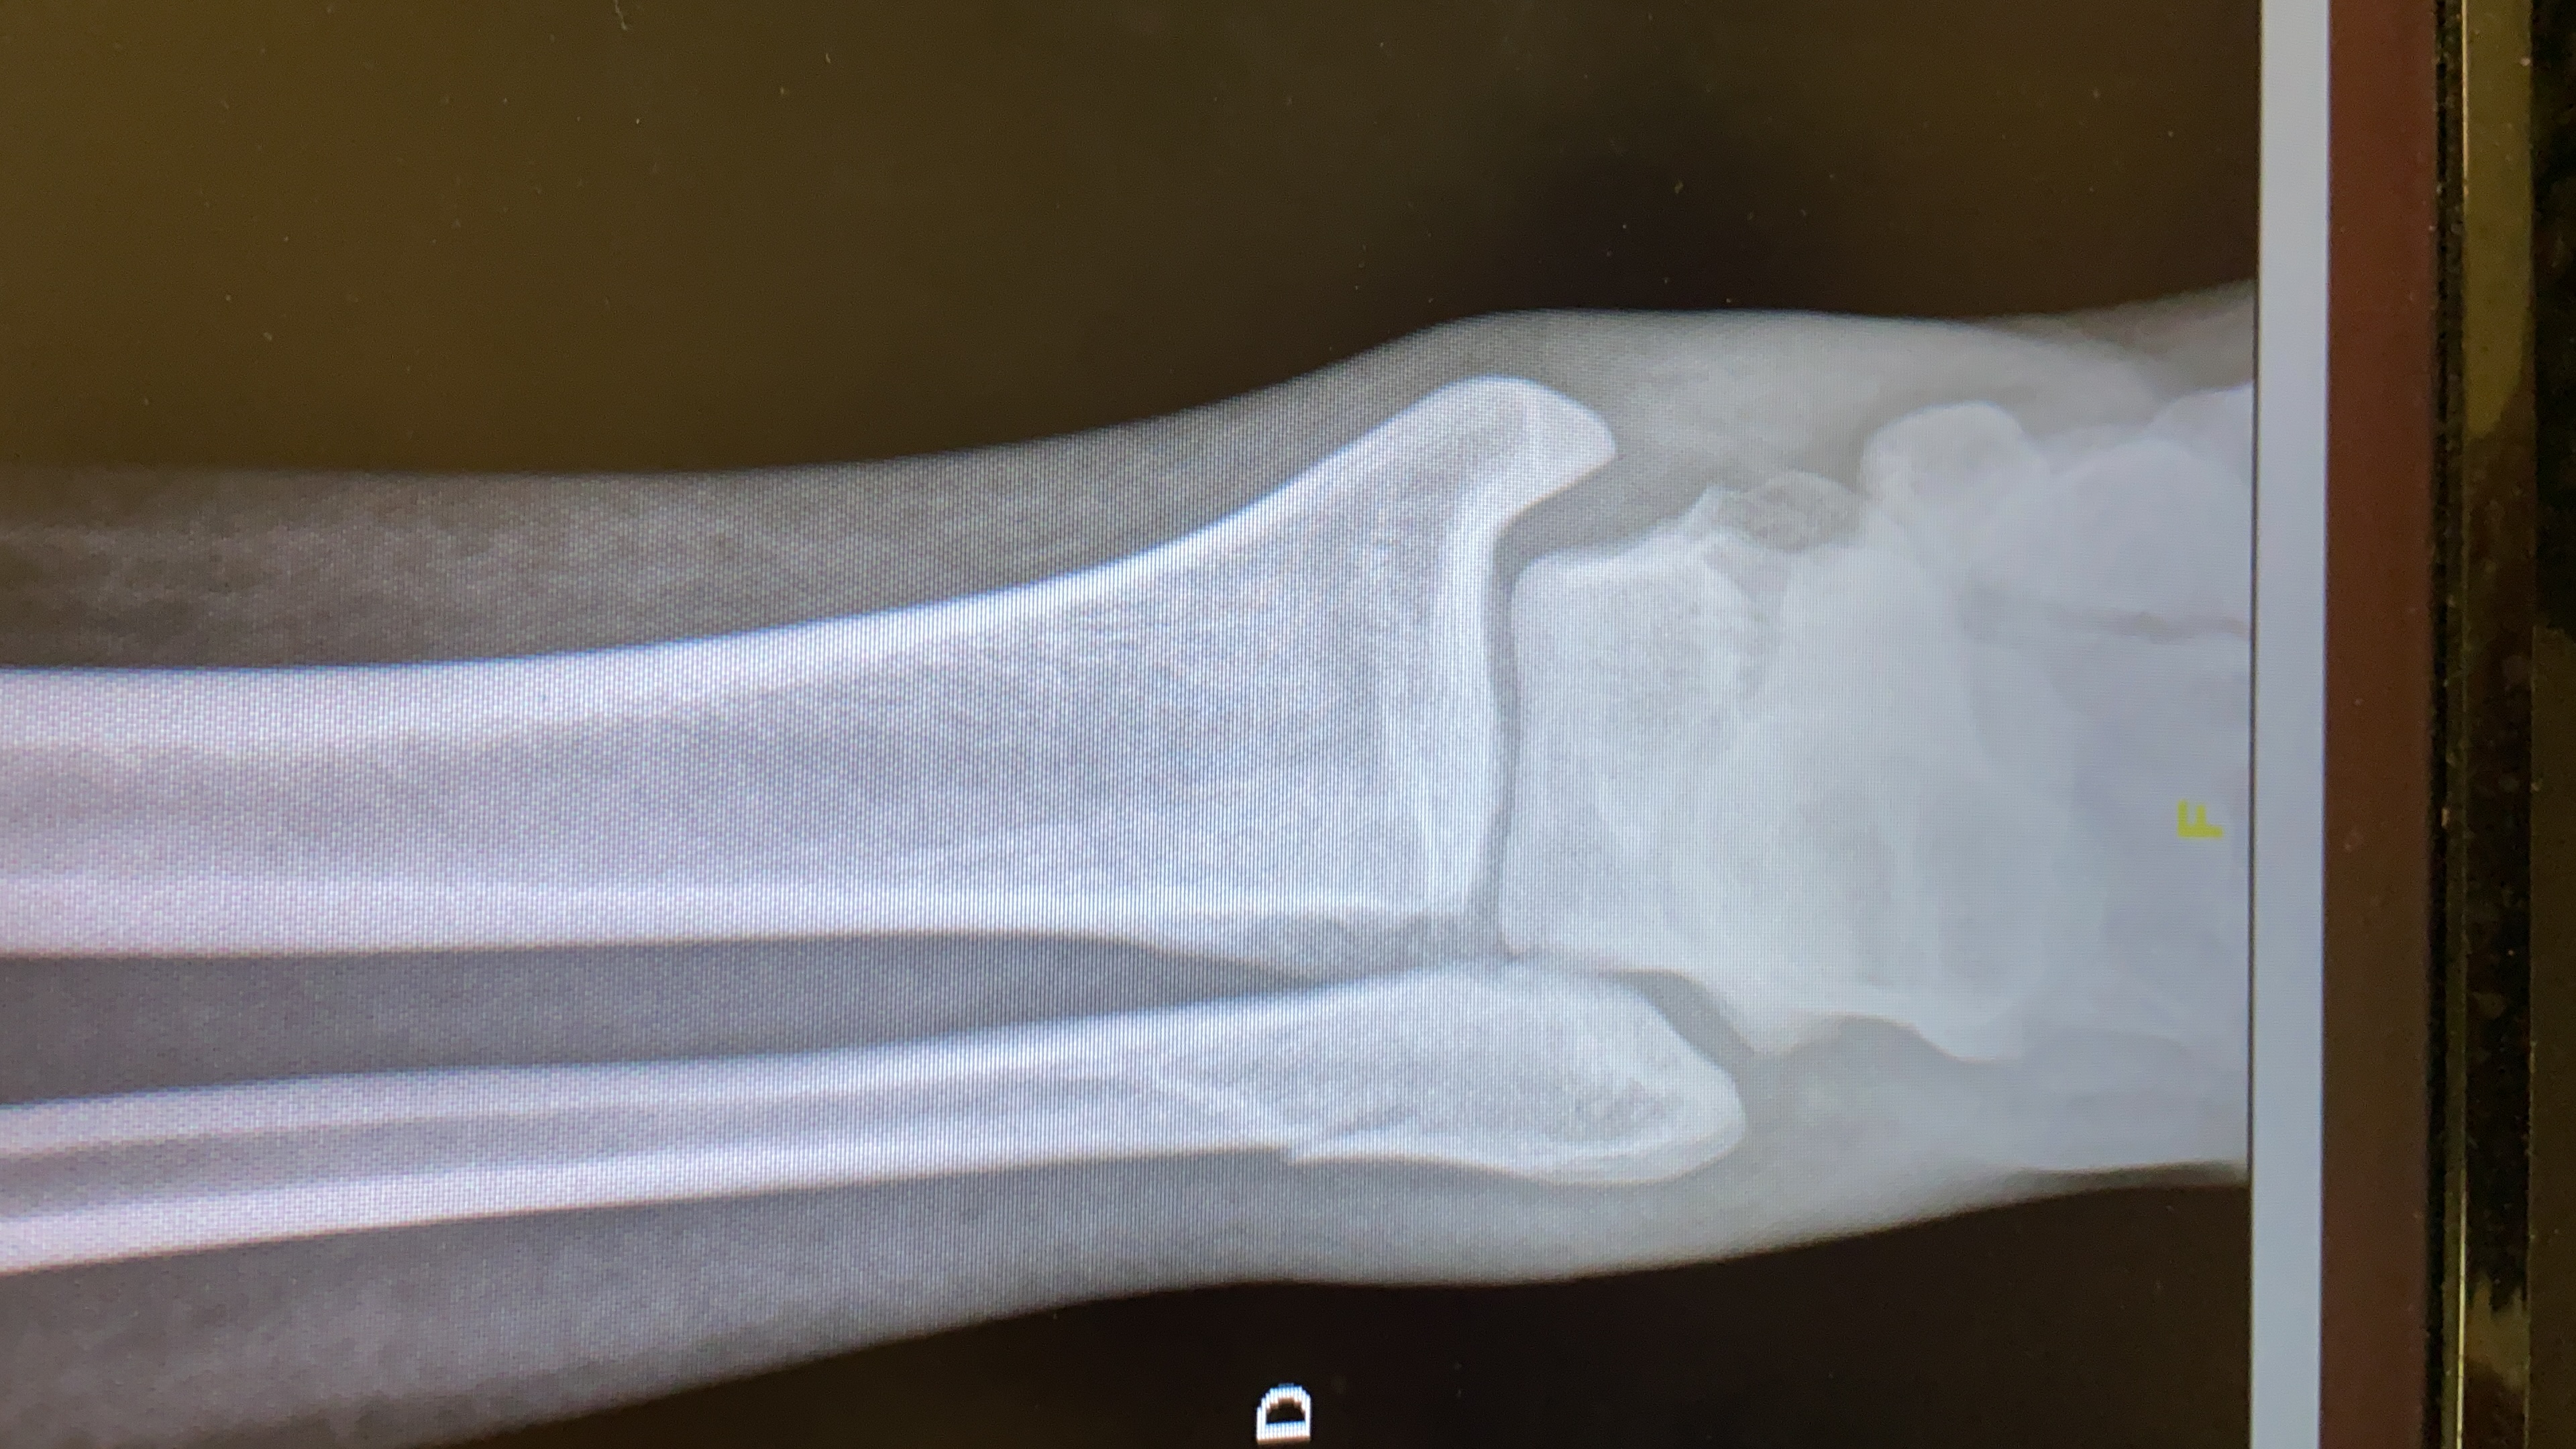

Fraturas do tornozelo

As fraturas do tornozelo podem ser resultantes de uma ampla variedade de trauma. Traumas de baixa energia tais como entorses ou de alta energia como acidentes de trânsito. São lesões comuns na prática...